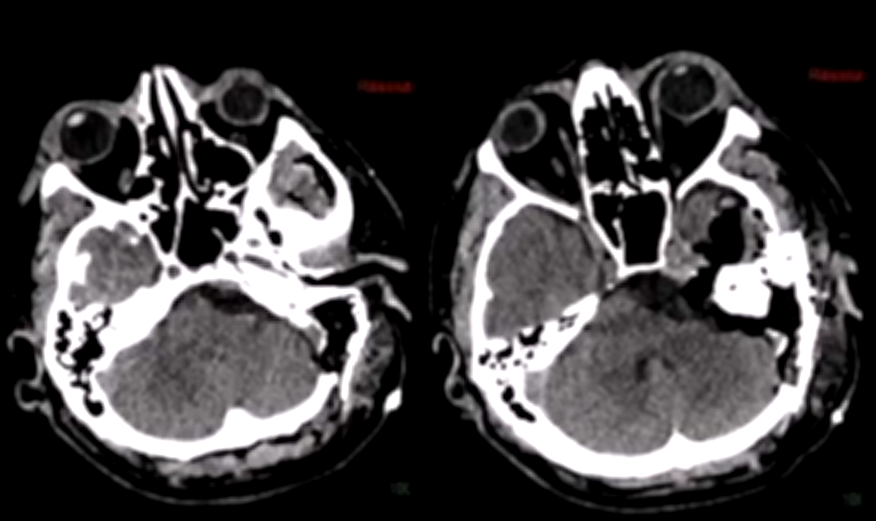

第二步是术前血管栓塞:在正式手术前,经介入手段在咽升动脉处置入栓塞线圈,提前切断肿瘤供血来源,大幅压缩术中出血量,为后续操作争取更充裕的术野空间。

术后MRI显示:肿瘤几乎完全切除,脑干压迫已彻底解除。术后CT未见任何并发症,颅骨修复状态良好。

术后恢复过程中,Bruno出现了一过性不完全性滑车神经麻痹,低头时有轻微复视,但该症状在术后3个月内完全消失;因中耳炎引起的轻度听力下降,也在术后6个月时完全恢复正常。